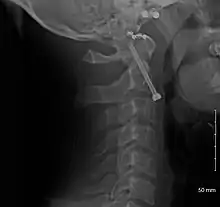

A fracture of the base of the dens as seen on plain X-ray

A fracture of the base of the dens as seen on CT

Type 3 odontoid fracture

Type 2 dens fracture